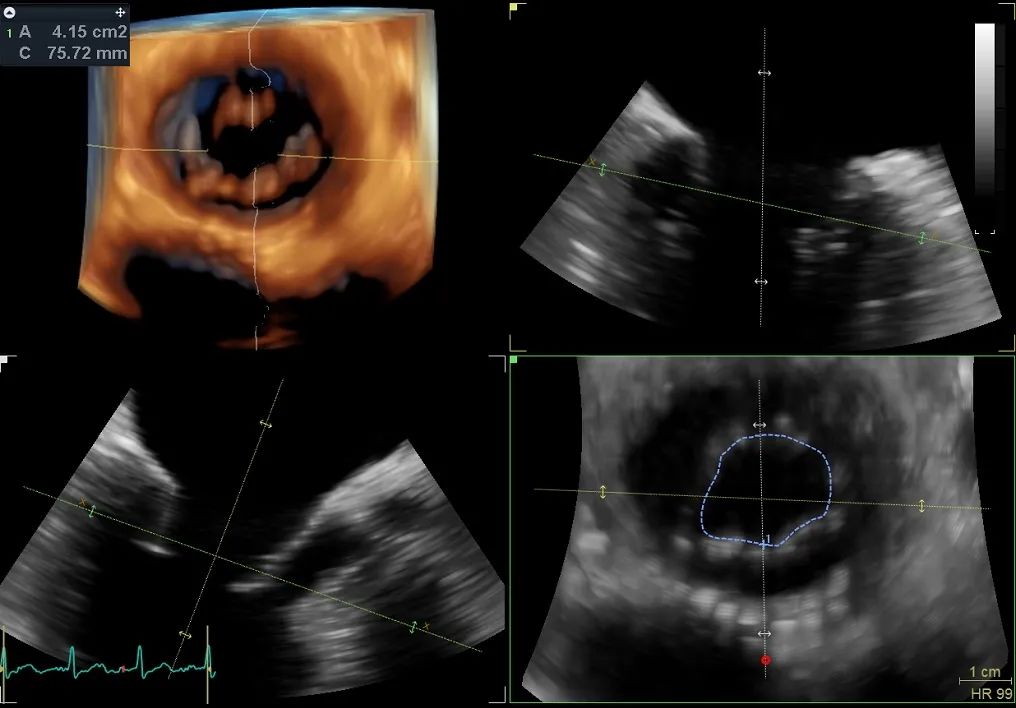

术前行经食道超声评估

原发性二尖瓣反流,反流程度4+;二尖瓣瓣口面积4.15cm²,平均跨瓣压差5mmHg,二尖瓣前叶(A2)长度23.35mm,二尖瓣后叶长度(P2)长度13.2mm;左室射血分数67%。患者手术风险高,操作难度大,经心脏瓣膜团队多次充分讨论评估后,决定行经导管二尖瓣缘对缘修复治疗。

术前MDT策略:从解剖结构来看二尖瓣后叶脱垂伴连枷涉及整个2区,累及3区和1区,宽度15mm左右,且连枷高度甩起高度有7-8mm,可见长达10.4mm的飘样回声,术前策略预计使用两个二尖瓣夹,较小的二尖瓣口面积和较高平均跨瓣压差,是一次高难度的挑战。